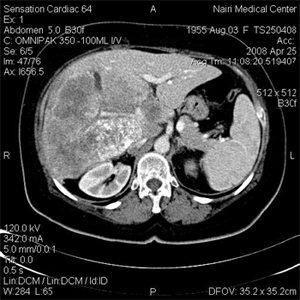

Многослойная КТ с тонкими срезами обычно позволяет решить такие проблемы при поражениях размером более 3-4мм, но может создать новые проблемы, отображая еще более мелкие очаги поражения. Однако сканирование в интерстициальной фазе позволило надежно отличить мелкие кисты от гиперваскулярных опухолей, так как последние в этой фазе выглядят изоденсивными [1.2]. После контрастирования может наблюдаться псевдоусиление (до 10 HU) вследствие частичного обьемного усреднения с окружающей печеночной тканью. Перибилли- арные кисты были множетственные и располагались в воротах печени. У 6 больных при КТ с контрастированием наблюдалось ослабленное кровоснабжение в артериальной фазе, по сравнению с окружающей печеночной тканью. В тех случаях, когда доминировала узловая КТ характеристика опухоли, центральная часть опухоли была гиперденсной, а пери-ферическая область - гиподенсной, как в замедленной (поздняя фаза, фаза вымывания) фазе (рис.2), так и в артериальной фазе (рис.3).

Рис. 3. Контрастусиленная КТ в артериальной фазе: многоузловая ГЦК с гиперваскулярной структурой